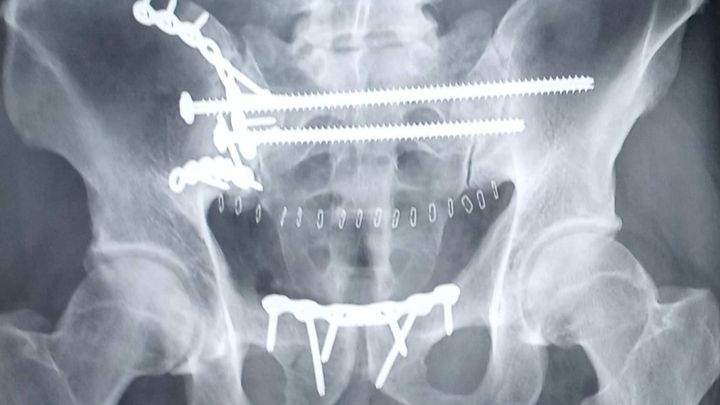

It's with a heavy heart that I am here to inform you about my brother Joel who was severely injured in a terrible motorcycle accident. As some of you may know, last Thursday as Joel was leaving work, he lost control and crashed into a solid brick pillar. He was immediately taken to the hospital and admitted into the ICU. He endured 5 broken ribs which caused his lung to collapse. He had to be put on a ventilator to breathe. The next major issue the doctors found was that he was suffering from the most severely shattered pelvis that the surgeon had ever seen. There was damage found to his kidney, bowel, and he had a laceration on his liver.

Well that was not the worst. Later that Thursday night, he had internal bleeding and was rushed to have emergency surgery to remove his spleen that nearly ruptured and a portion of his large intestine was removed as well. The next hurdle was surgery on his pelvis. He was given a total of 5 units of blood with both surgeries. We have also been informed that he has a few broken vertebrae, bone fragments in his shoulder (which will need surgery as well) and even though he is off of the ventilator, he is in severe pain.